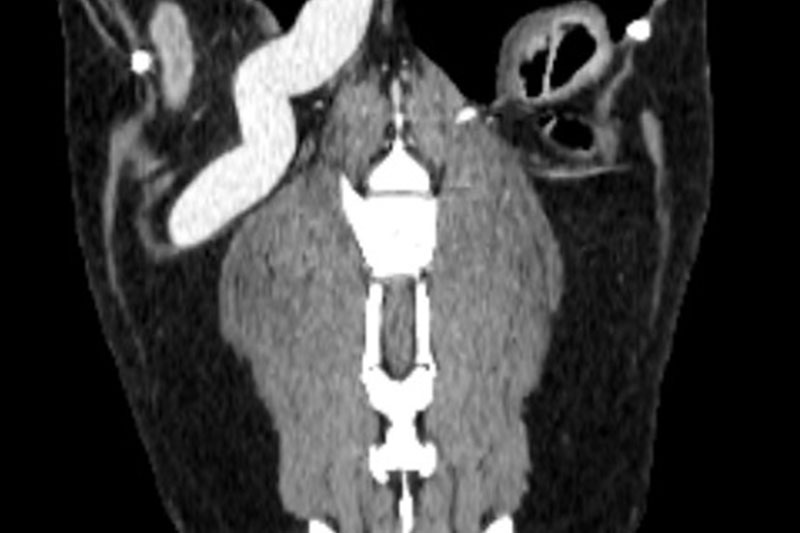

CT (Computed Tomography, 전산화 단층촬영) 검사는 X-ray를 이용해 반려동물의 몸을 여러 각도에서 촬영하고, 이를 컴퓨터로 합성하여 단면 이미지(슬라이스)를 만들어내는 정밀 진단 장비입니다.

사람 병원에서도 널리 사용하는 기술로, 뼈, 장기, 혈관, 종양 등 몸속 구조를 3차원(3D)으로 시각화할 수 있습니다.

| 두부(머리) | 뇌종양, 두개골 골절, 중이염, 치주염, 안와(눈) 질환 등 |